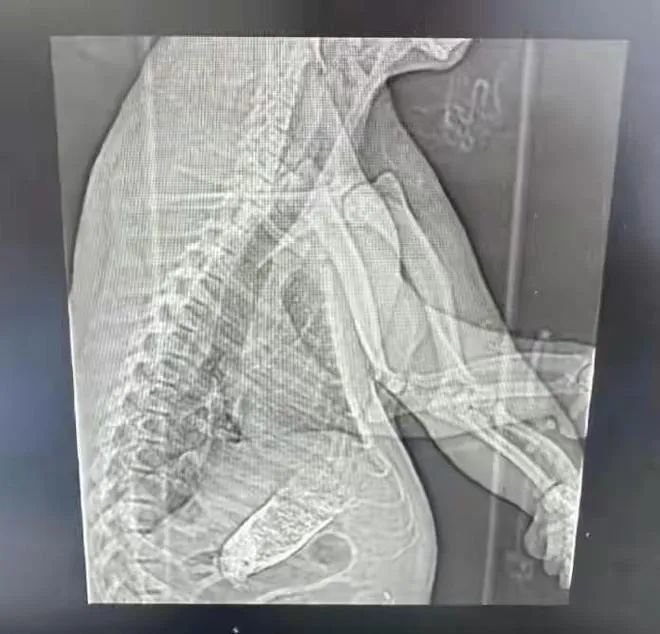

2月27日,“七七”被送往上海仁济医院进行胸腹部CT检查,CT报告确诊“七七”肠梗阻。

东方网记者从知情人士处获悉,确有一名“熊猫患者”被送至仁济医院南院。检查结果显示,这名“患者”有肠梗阻的情况,还伴有一些腹水。